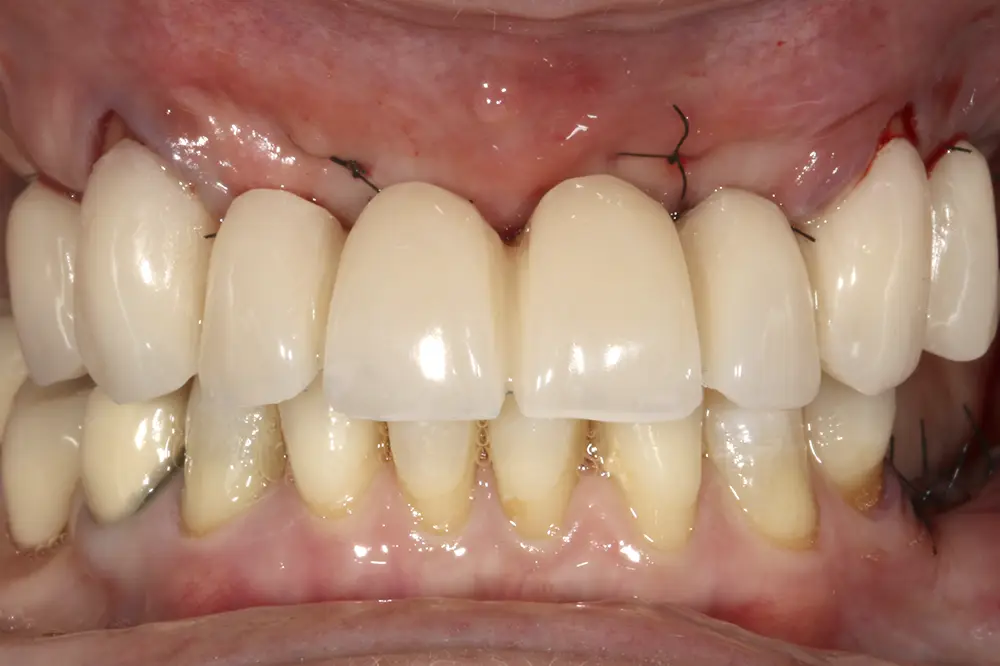

Transcurridos cuatro meses desde la fase inicial, ya tenemos suficiente hueso disponible en las zonas donde se realizaron las extracciones y regeneraciones con PRGF-Endoret, por lo que podemos planificar la colocación de implantes en estas áreas en un segundo tiempo quirúrgico. En el primer cuadrante, en los cortes del cone-beam realizado en este momento podemos observar una regeneración completa del alveolo tanto del molar como del premolar extraídos en la primera fase y cómo podemos colocar implantes, cortos y estrechos también en estas localizaciones (figs. 27-28). En esta fase, se aprovecha además para extraer los dos caninos que han cumplido con su función de permanecer durante la fase inicial de provisionales y cargar ya los implantes superiores de la primera fase con una prótesis atornillada mediante transepitelial múltiple y una estructura de barras articuladas, que permitirá de forma sencilla posteriormente ir añadiendo aquellos implantes que quieran cargarse seguidamente sin necesidad de repetir la estructura completa (figs. 29-31).

Figs. 29-30. Imágenes de la prótesis de carga progresiva, ya apoyada sobre los implantes superiores.

Fig. 31. Imagen de la carga de los implantes superiores de la primera fase y los dos colocados en esta segunda fase que se dejarán en dos tiempos. En este punto se lleva a cabo también la exodoncia de los caninos.